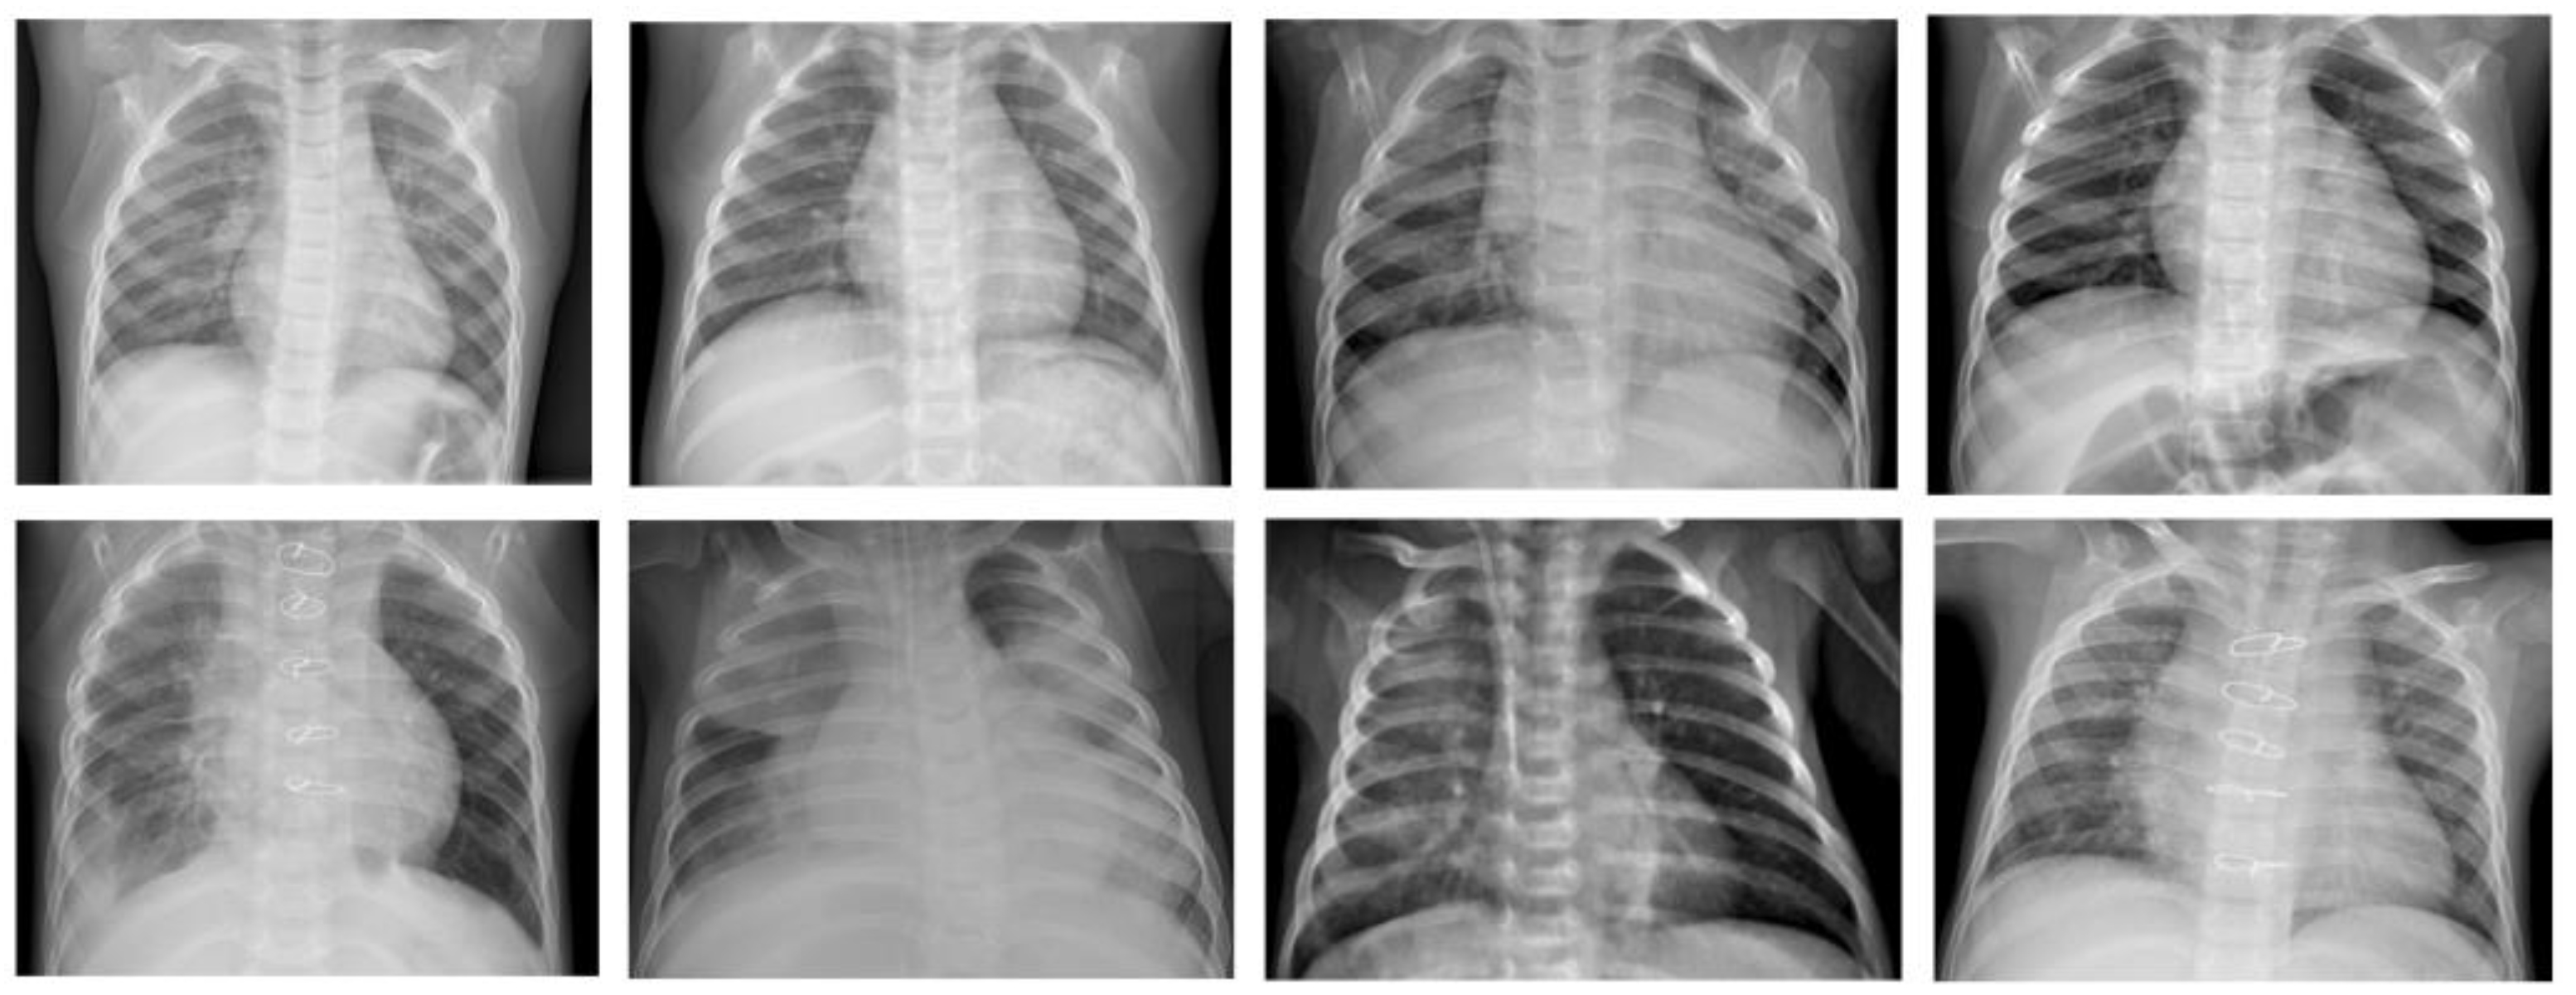

Since computer programs cannot be impacted by fatigue or distractions, they are generally reliable once properly trained for the given task. Furthermore, it is possible with AI programs to evaluate several chest X-ray records over a short period; a human examiner usually requires more time to evaluate the same number of chest X-ray records due to fatigue. The ML model that that is investigated in this work is the β-VCAE and its variants. Figure 1 shows some samples of the chest X-rays used in this work.

Figure 1. Chest X-ray samples used in this paper [24]. Top row: X-ray samples with no pneumonia. Bottom row: X-ray samples with pneumonia.